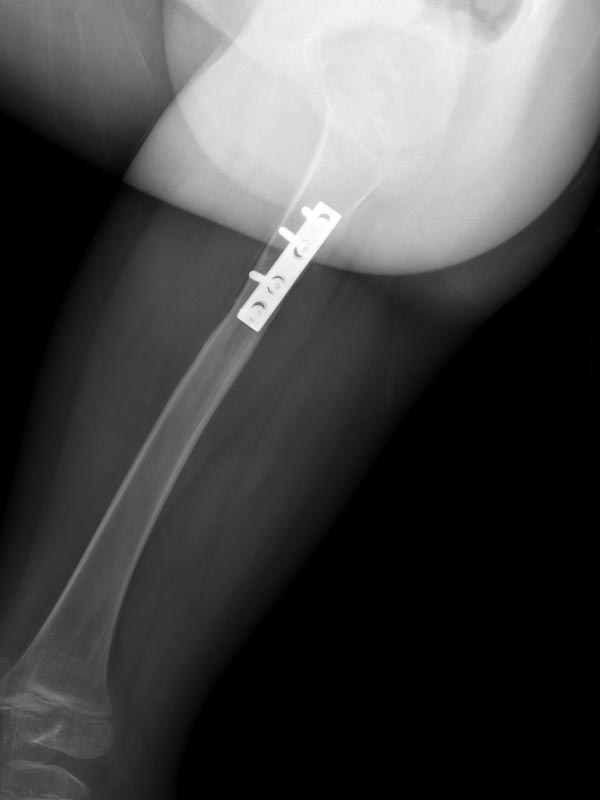

Caso No. 2 - Enfermedad de Blount derecha

Preoperación

Posoperación

Enfermedad de Blount derecha

Diagnóstico: Enfermedad de Blount derecha (deformidad mixta de la tibia tanto frontal y rotacional)

Tratamiento quirúrgico: osteotomía correctiva y fijación externa Taylor Spatial Frame